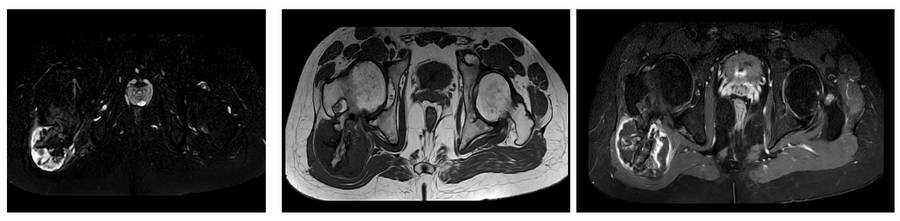

Before the surgery: The MRI shows a cartilage cap and edema around the tumor.